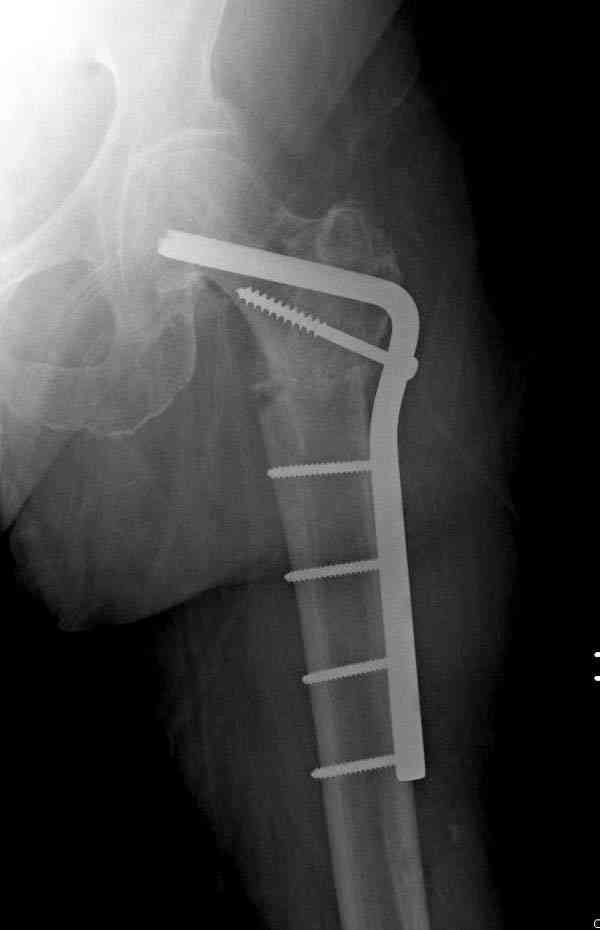

[Ortho] Ятрогенный подвертельный перелом

Не стали усложнять интрамедуллярным вариантом коррекции, легче контролировать коррекцию пластиной, поэтому сделали операцию 95 градусной Blade Plate, разогнув до 110 градусов.

Надеемся на успех, потому что до введения пластины дефект от импланта забили костной стружкой и удалось создать компрессию между отломками, максимальную для импланта (150 кило/паунд). Сделана дополнительная костная пластика и за счет измененного угла пластины устранено укорочение конечности.

Допущенные прежним врачом тактические и технические ошибок мы разобрали на нашей конференции по ошибкам "M&M".